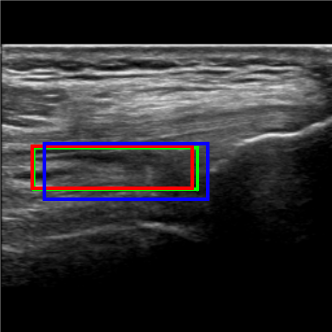

Considering the detection problem, Figure 10 shows US images where the two approaches detected the SQR with the lowest and the highest IoU. In Figure 10a, the Multi-task approach wrongly detects as SQR an image region that is similar to an actual SQR in terms of position and shape, resulting in a very low value of IoU (0.330.330.33). In this case, also the Detection approach can not reliably detect the right target precisely, and indeed it detects only a small portion of the actual SQR (IoU=0.330.330.33). Instead, in the example shown in Figure 10b the Multi-task approach accurately detects the SQR (IoU=0.950.950.95), while the Detection approach identifies the same area with a lower IoU (0.68)0.68).

Figure 10c shows the US image for which the Detection approach provided the lowest IoU value. The problem is similar to that of Figure 10a: a region is erroneously recognized as a SQR because it is similar to a SQR. In this case the detected bounding box does not overlap with the ground truth, hence the IoU is zero. Instead, the Multi-Task approach basically detects the right target (IOU=0.580.580.58).

Refer to caption

(a) Worst detection by Multi-Task approach

(b) Best detection by Multi-Task approach

(c) Worst detection by Detection approach

(d) Best detection by Detection approach

Figure 10: Detection examples. Green represents the ground truth, red and blue the results of the Multi-Task approach and Detection approach, respectively.

Figure 10d shows instead the US image for which the Detection approach provided the highest IoU value (0.960.960.96). In this case the Multi-task approach identifies the right target less precisely, resulting in a IoU of 0.550.550.55.